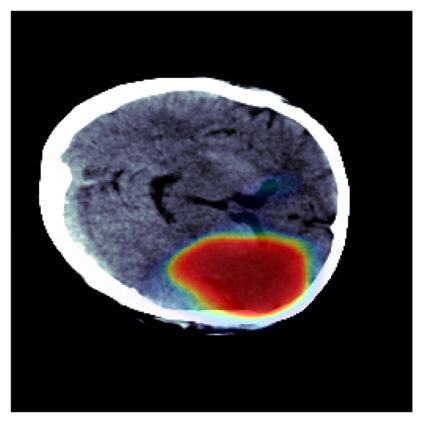

The sigmoid activation is the standard output activation function in binary classification and segmentation with neural networks. Still, there exist a variety of other potential output activation functions, which may lead to improved results in medical image segmentation. In this work, we consider how the asymptotic behavior of different output activation and loss functions affects the prediction probabilities and the corresponding segmentation errors. For cross entropy, we show that a faster rate of change of the activation function correlates with better predictions, while a slower rate of change can improve the calibration of probabilities. For dice loss, we found that the arctangent activation function is superior to the sigmoid function. Furthermore, we provide a test space for arbitrary output activation functions in the area of medical image segmentation. We tested seven activation functions in combination with three loss functions on four different medical image segmentation tasks to provide a classification of which function is best suited in this application scenario.